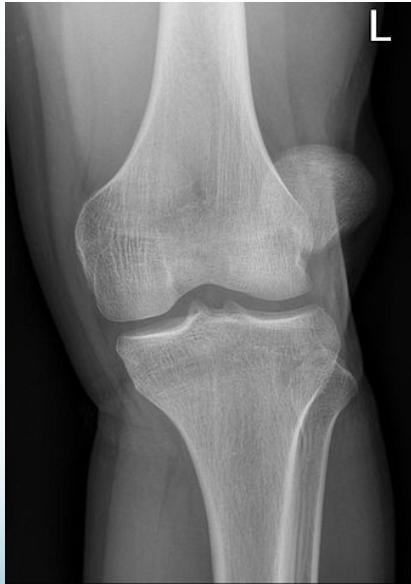

X-rays: Standard knee radiographs

X-ray Findings:

- Dislocation

- Fractured tibial spine (cruciate ligament avulsion)

- Avulsion fibular styloid (collateral ligament avulsion)